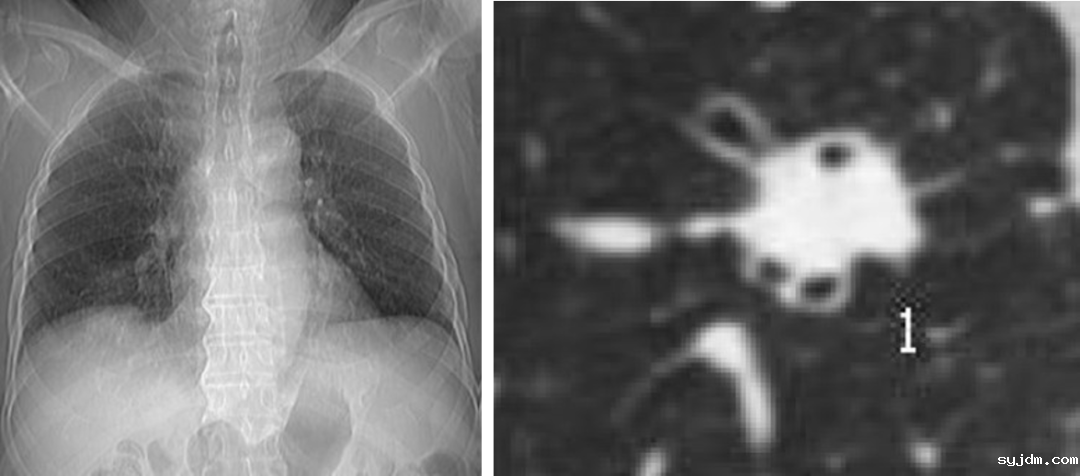

胸片(左图)看不见肺结节,CT(右图)清晰地显示肺结节,最后证实该结节为肺癌

胸片仅能发现直径大于13mm的肺结节,用胸片来发现早期肺癌,哪怕阅片经验丰富,水平很高的医生也难免漏诊肺内较小的病灶,往往中晚期肺癌被检出,而早期肺癌却漏掉了,“年年体检都正常,一发现肺癌就是晚期”的悲剧常有发生。由较有经验的医生来判读CT图像,如果还辅以AI,可以检出全部肺结节。